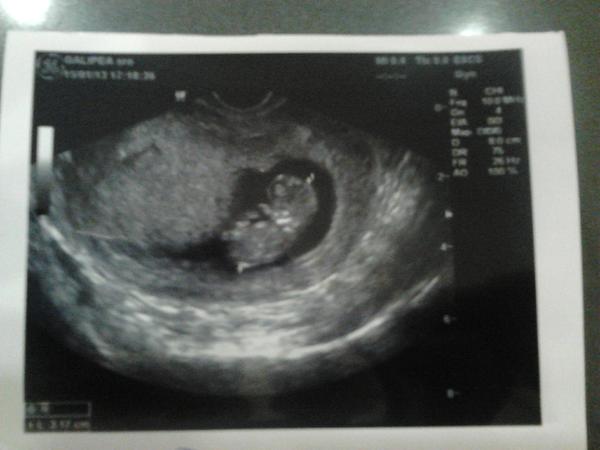

ahojte kocky,tak aj ja som dnes bola na ultrazvuku a vsetko mame v poriadku.babo ma 59,00mm 🙂 ak som dobre vycitala z papierov....jooj uz si to pomalicky zacinam aj uvedomovat,ze budeme rodicmi 🙂

@katarinka_brnka jeeeeej, ako nadherne ho/ju vidno 🙂 krasa!